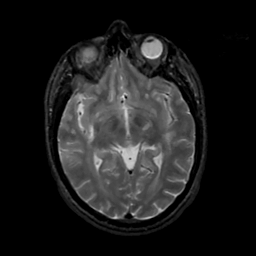

MR Study #8, March 31, 1991 -- Slice #23